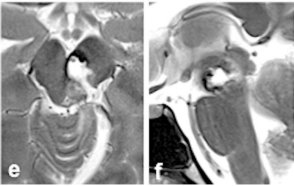

脑干海绵状血管瘤易反复出血,为最大限度挽救生命提高生活质量,治疗关键在于安全手术全切。治疗之路无捷径可走。最终,经多方查询,他们找到INC巴特朗菲教授。巴教授仅剔除部分头发,为她保留长发。最终顺利全切海绵状血管瘤,矢状(f)MRI证实病灶完全切除。

尽管出现暂时性动眼神经麻痹,但几周内逐渐恢复,未遗留任何神经功能缺损。更令人鼓舞的是,爱丽丝不仅重获健康,更重新踏上马拉松赛道,用奔跑诠释生命韧性。